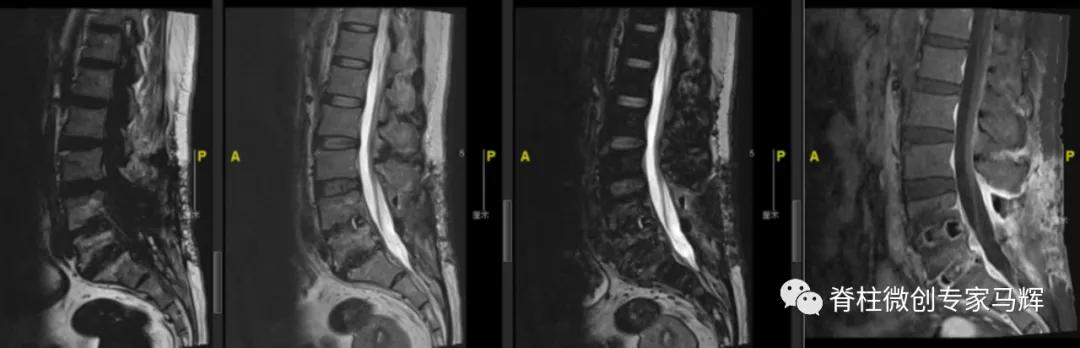

54岁的张女性,因为左髋部疼痛,行走不便2天,在当地医院就诊。查CT显示腰椎骨质增生,L2-3、L3-4椎间盘膨出。L4-5、L5-S1椎间盘术后改变,部分椎板缺如。L5-S1硬膜囊及右侧神经根受压而显示不清。入院后予以抗感染、活血等相关对症治疗,症状无明显缓解,当地医院建议转上级医院进一步诊治。为此,张女士一家慕名来到了上海第九人民医院脊柱外科就诊。

入院的时候,张女士有腰痛,左下肢疼痛无力伴发热6天,近3日疼痛加剧,翻身抬腿困难,发热最高达到38°C。根据症状,体格检查,实验室检查和影像检查,判断张女士可能存在脊髓硬膜外脓肿(SEA)压迫神经,以及感染的情况。为什么会出现这种状况呢?

最近这几年的手术经历让张女士的身体状况不是很好,可能存在免疫力存低下的情况。脊柱手术后可能存在医源性感染种植,进一步的腰椎间盘膨出,让张女士更容易出现脊髓硬膜外脓肿(SEA)感染的情况。SEA可通过血行播散或者通过邻近椎间盘炎或骨髓炎直接蔓延。

对于无神经症状的SEA患者可采取单纯药物治疗。出现神经受压表现的患者需要采用外科减压术和抗生素治疗,以避免出现瘫痪的可能。经过讨论后,马辉主任团队决定对张女士进行脊柱后路脓肿清除加置管持续冲洗术,并进行血培养和脓液培养检查寻找可能的致病病原。

术中通过后外侧切口良好地显露了病灶范围,进行彻底的病灶清除,去除了压迫脊髓的脓肿,彻底清创之后进行一期闭合和加置管灌洗。术后患者腰痛及下肢疼痛马上消失,下肢活动自如,无明显麻木感。脓液培养提示金黄色葡萄球菌感染,予以敏感抗生素抗感染治疗。目前病情平稳,近期佩戴支具就可下地行走。